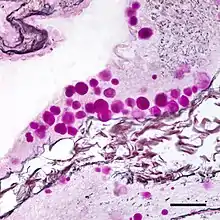

Corpora amylacea (CA) (from the Latin meaning "starch-like bodies") is a general term for small hyaline masses found in the prostate gland,[1] nervous system,[2] lung,[1] and sometimes in other organs of the body.[3] Corpora amylacea increase in number and size with advancing age,[3][4] although this increase varies from person to person.[3] In the nervous system, they are particularly abundant in certain neurodegenerative diseases.[2] While their significance is largely unknown, some researchers have suggested that corpora amylacea play a role in the clearance of debris.[1][3]

The composition and appearance of corpora amylacea can differ in different organs.[3] In the prostate gland, where they are also known as prostatic concretions, corpora amylacea are rich in aggregated protein that has many of the features of amyloid, whereas those in the central nervous system are generally smaller and do not contain amyloid.[3] Corpora amylacea in the central nervous system occur in the foot processes of astrocytes, and they are usually present beneath the pia mater, in the tissues surrounding the ventricles, and around blood vessels.[2] They have been proposed to be part of a family of polyglucosan diseases, in which polymers of glucose collect to form abnormal structures known as polyglucosan bodies.[3] Polyglucosan bodies bearing at least partial resemblance to human corpora amylacea have been observed in various nonhuman species.[3]